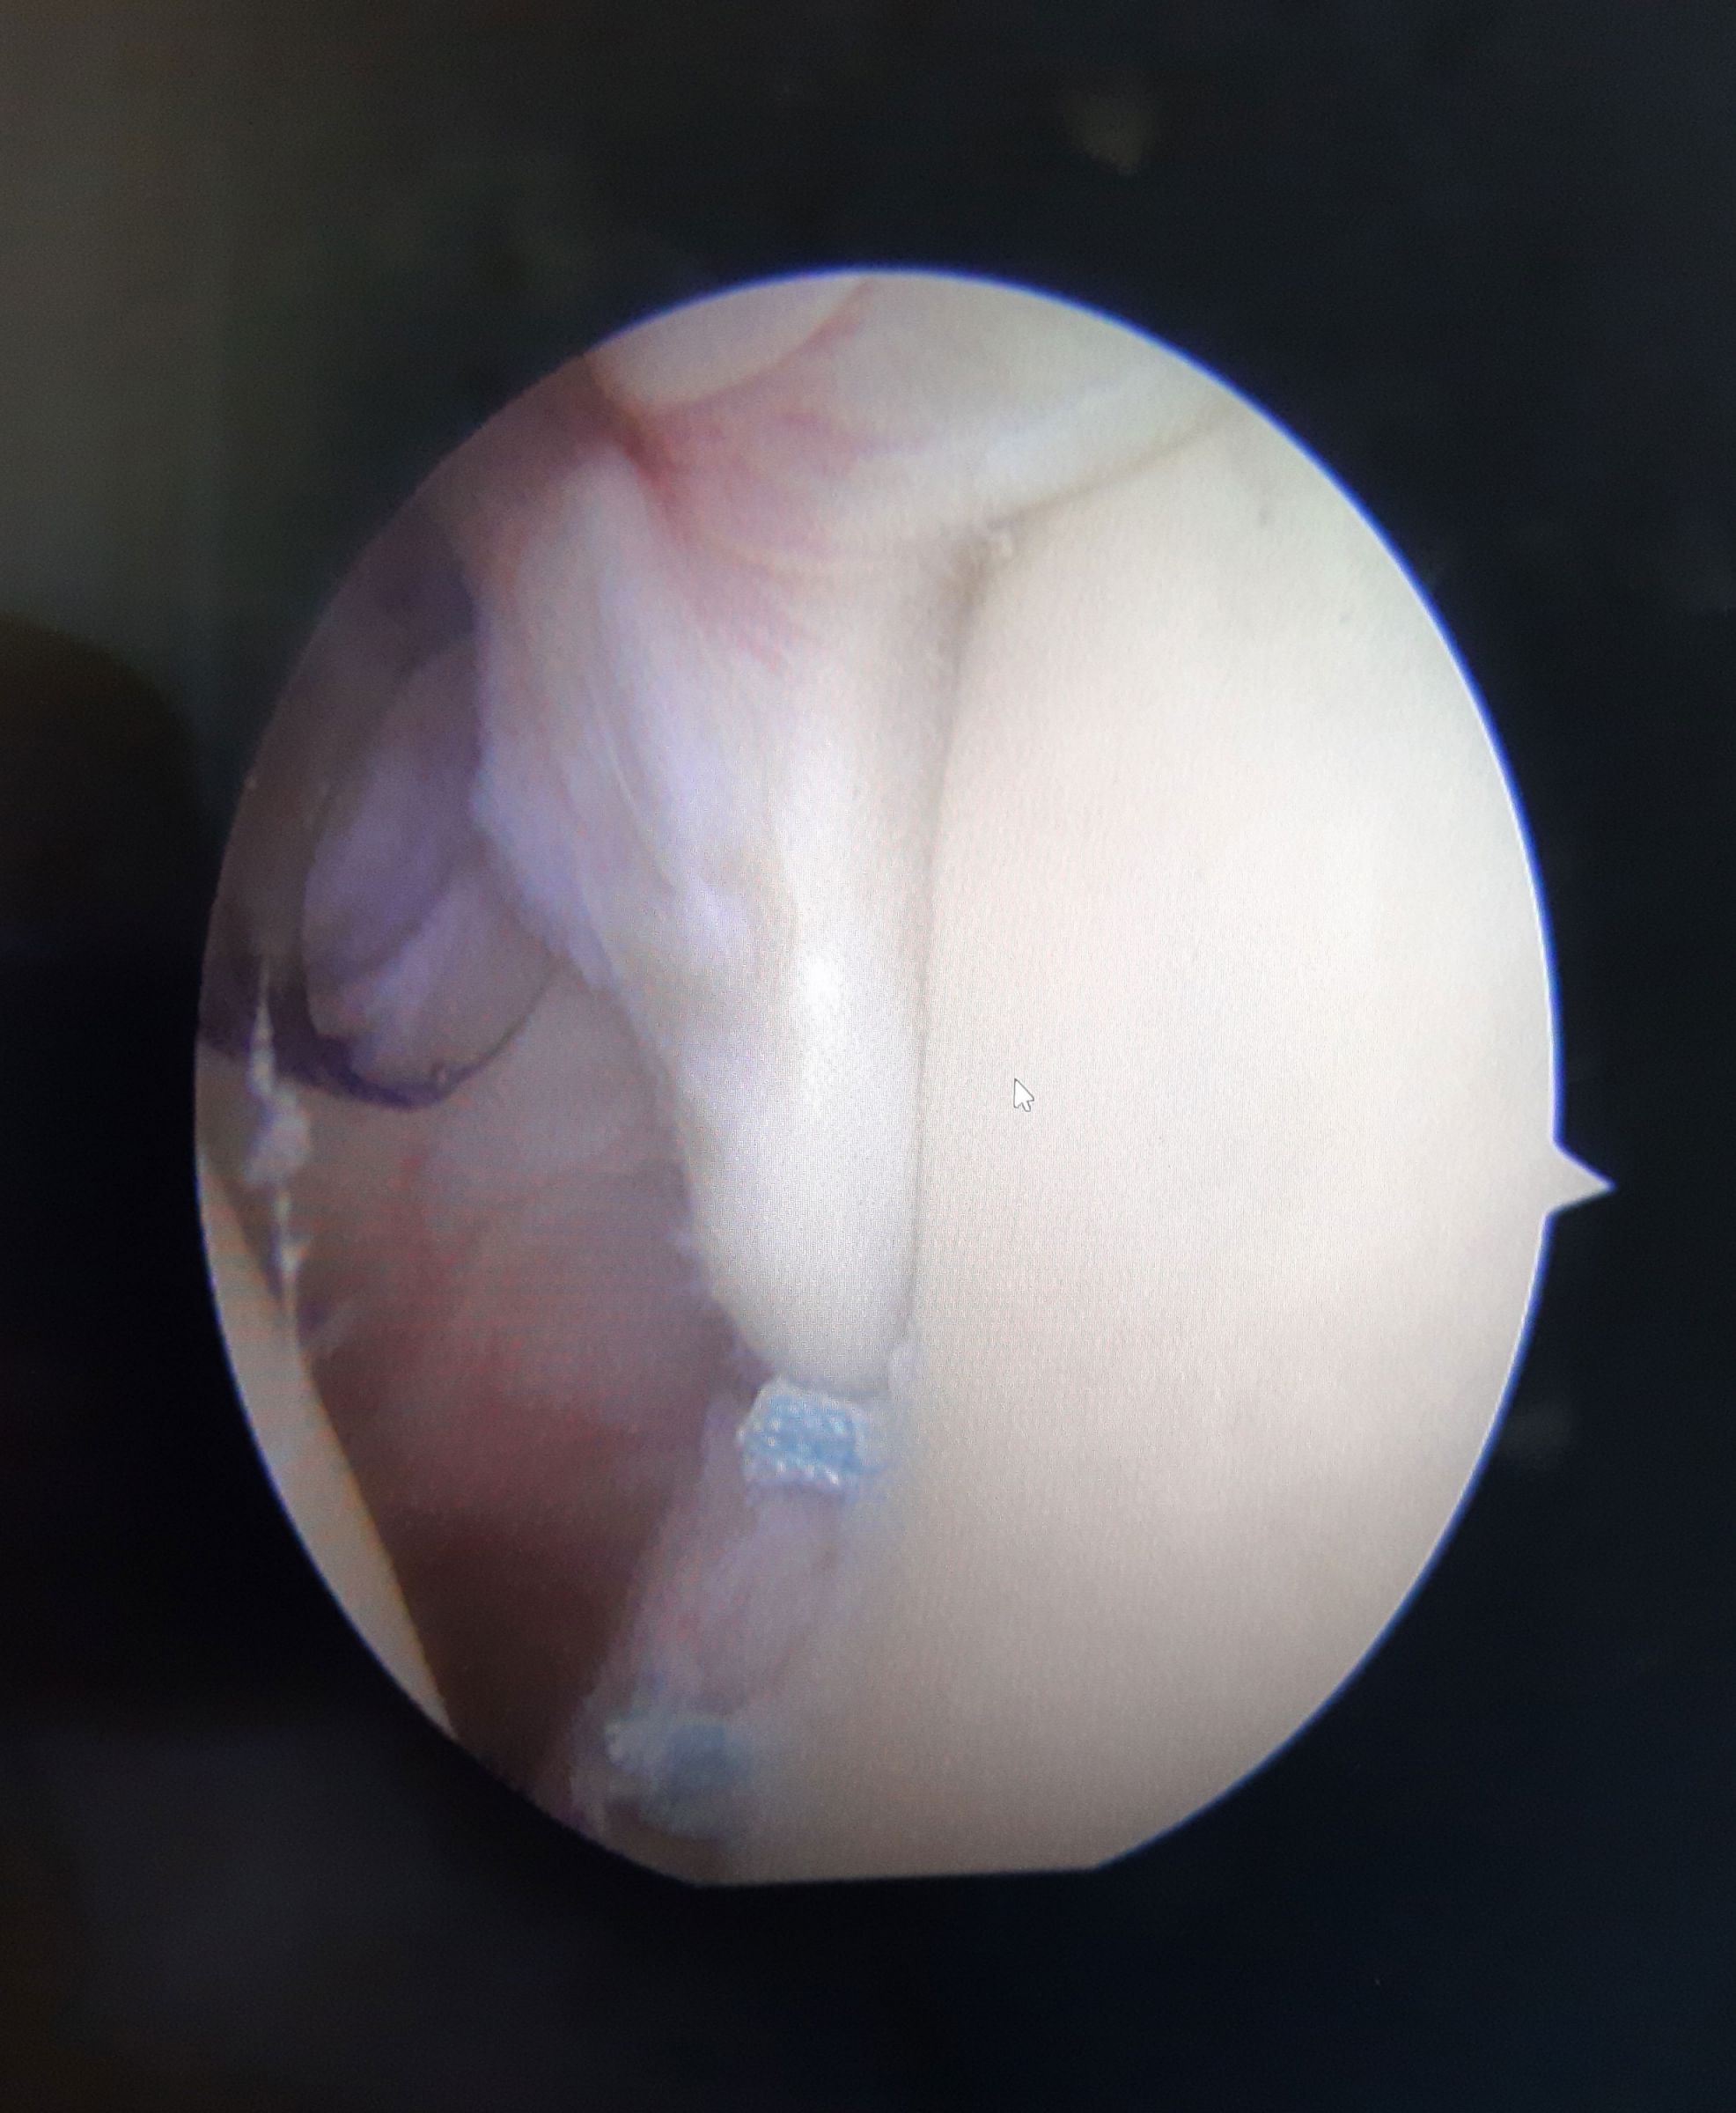

Bei der erstmaligen Luxation kann in der Regel ein arthroskopischer Eingriff durchgeführt werden. Hierbei wird das Labrum mit Nahtankern wieder am Knochen refixiert.